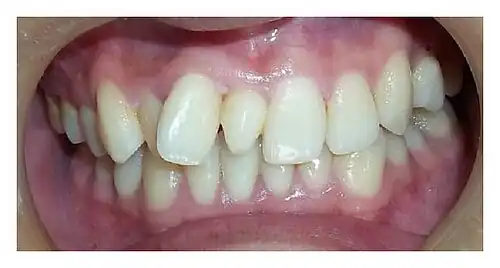

Presentación clínica de un diente supernumerario anterior (Mesiodens).